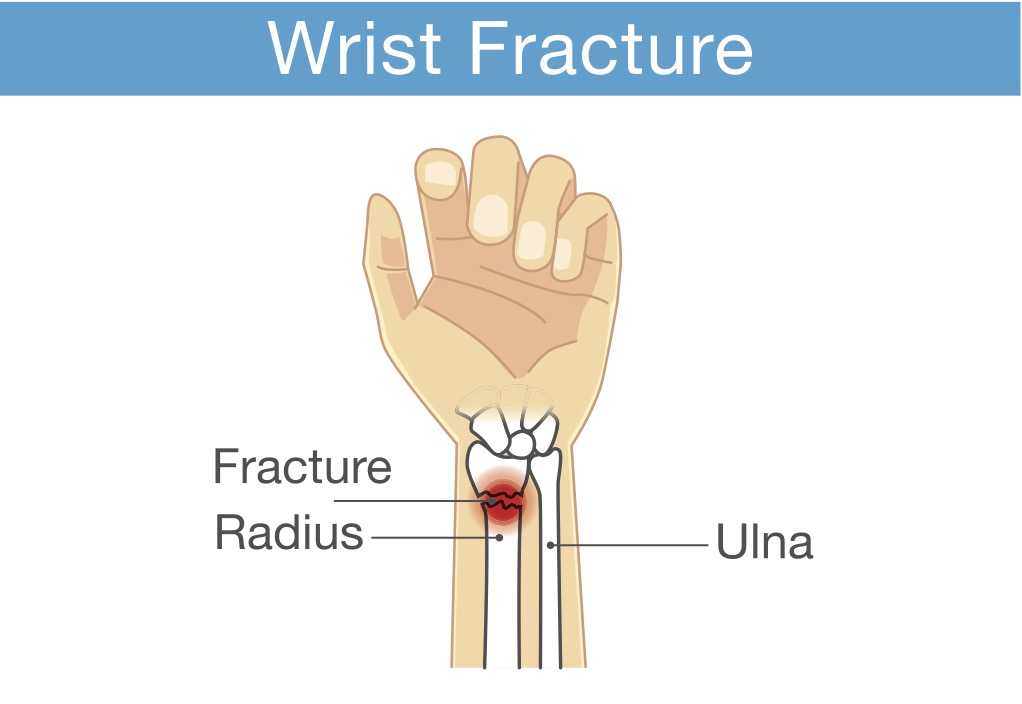

桡骨远端骨折手术修复后有目的的活动的重要性

作者:Kelsey Melton Collis, JM、Mayland, EC、Wright-St Clair, V.、Rashid, U.、Kayes, N. 和 Signal, N.(2022)。手腕和前臂的评估...

老年患者桡骨远端骨折掌侧锁定钢板接骨后的早期活动:随机对照试验

作者:Rachel Reed Sørensen, TJ、Ohrt-Nissen, S.、Ardensø, KV、Laier, GH 和 Mallet, SK (2020)。掌侧锁定钢板后早期活动...

使用压缩手套治疗桡骨远端骨折

使用压缩手套治疗桡骨远端骨折 Miller-Shahabar, I.、Schreuer, N.、Katsevman, H.、Bernfeld, B.、Cons, A.、Raisman, Y. 和 Milman, U. (2018)。功效...

肥胖或吸烟会改变桡骨远端骨折的结果吗

Hall, Matthew J.、Ostergaard, P.、Dowlatshahi, A.、Harper, C.、Earp, B. Rozental, T. (2019)。肥胖和吸烟对掌侧钢板术后结果的影响......